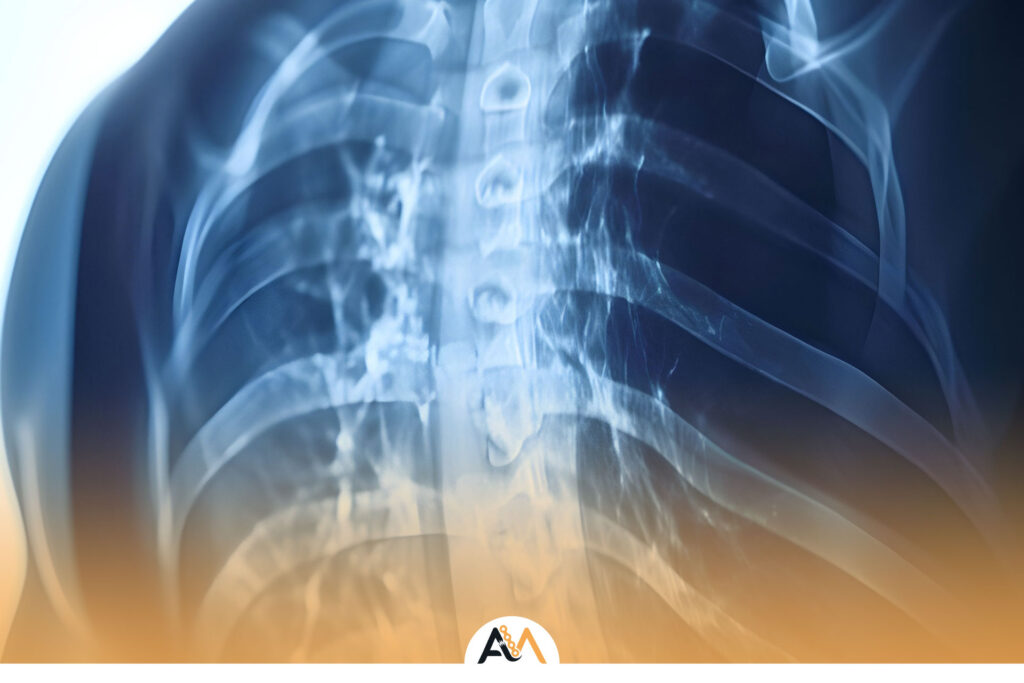

درمان شکستگی دنده ها: مدیریت درد و روش های بهبودی سریع

شکستگی دنده ها یکی از شایعترین آسیبهای ناحیه قفسه سینه است که میتواند به دلایل مختلفی مانند تصادف، سقوط از ارتفاع یا حتی سرفه شدید رخ دهد. این آسیبها معمولاً دردناک هستند و نیاز به مراقبت و درمان مناسب دارند تا از عوارضی مانند آسیب به ریهها، عفونت یا مشکلات تنفسی جلوگیری شود. در این […]